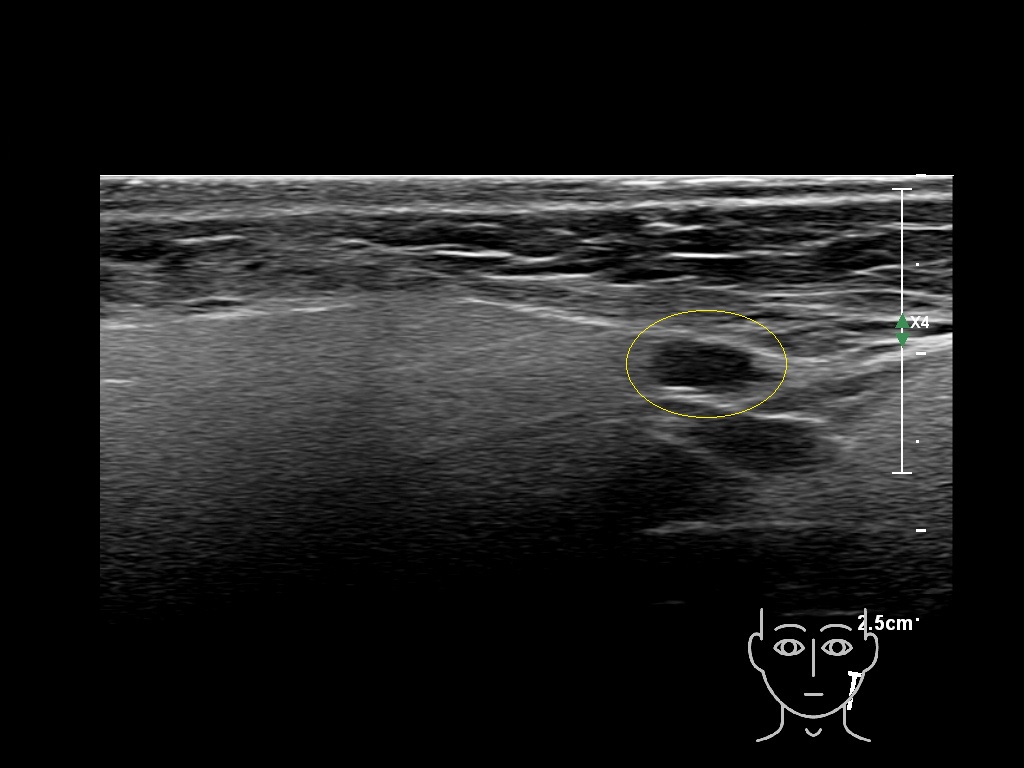

Filler injections in the parotid gland may go unnoticed, however, inflammatory reactions and abscesses may occur. Hypervascularity can be seen with color doppler. Filler deposits are supposed to be injected into the superficial fatty layer . The space to inject into this layer may be limited. Routinely we measure a width of 2-4 millimeters with sometimes subcutaneous layers being less than one millimeter thick.

Study the first image to recognize the different layers. If you are sure about the layers, swipe to the second image to view the answer (if applicable).